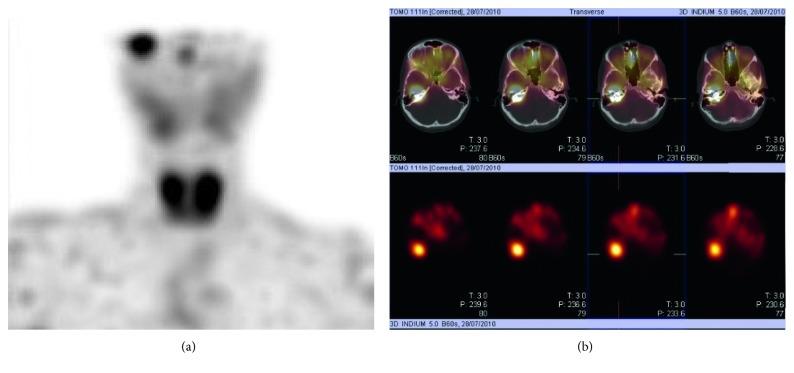

Middle ear adenomatous neuroendocrine tumor (MEANT) poses a diagnostic challenge. Clinical symptoms are nonspecific. Definite diagnosis is made by histopathological analysis of the tumor after a complete surgical resection based on an extensive computed tomography/magnetic resonance imaging (CT/MRI). Controversial terminology of the neoplasm arises from the differentiation of this tumor composed of both endocrine and exocrine glands. Middle ear (ME) localization is rare and less aggressive than gastrointestinal tract or lung localizations. Nevertheless, clinical and CT/MRI analyses are necessary follow-ups for preventing or detecting recurrence or metastasis. A case of a female patient aged 26 with recurrent middle ear neuroendocrine adenoma is presented herein.

中耳腺瘤样神经内分泌肿瘤(MEANT)带来了诊断挑战。临床症状不具有特异性。在基于广泛的计算机断层扫描/磁共振成像(CT/MRI)进行完整手术切除后,通过对肿瘤进行组织病理学分析来做出明确诊断。该肿瘤由内分泌腺和外分泌腺组成,其分化导致了该肿瘤有争议的命名。中耳(ME)定位罕见,且比胃肠道或肺部定位的侵袭性小。然而,临床及CT/MRI分析是预防或检测复发或转移的必要后续检查。本文介绍了一例26岁复发性中耳神经内分泌腺瘤的女性患者。